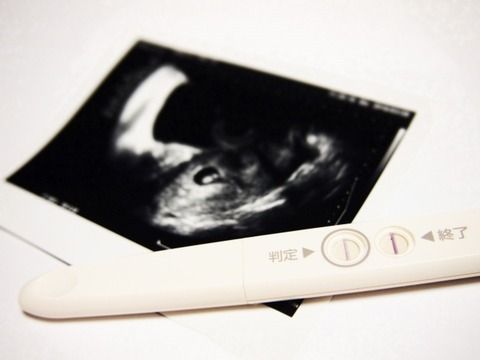

【やりきれない】三つ子を妊娠中の嫁が倒れた!医者「このままだと奥さんも赤ちゃんも危ない、どちらを優先しますか?」俺「…それは…」